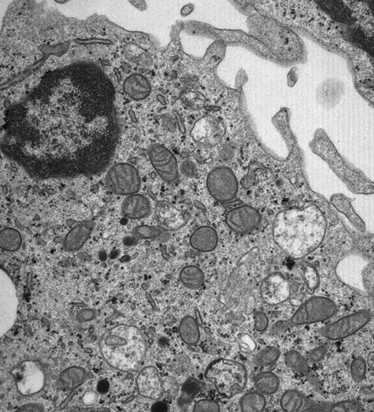

To that end we stimulated human monocytes (a type of innate immune cell) with various microbes and the Toll-like receptor ligands LPS and Pam3CysSK4 (P3C)*. We confirmed that upon activation with either of the microbial stimuli immune cells increased glycolysis; the quickest way to generate energy. Intriguingly however, LPS was the only stimulus that lowered OXPHOS. All the other stimuli did not affect or even increased OXPHOS. We decided to zoom in on this difference in metabolic regulation upon activation by comparing monocytes stimulated with LPS, which lowered OXPHOS, with monocytes stimulated with P3C, that did not alter OXPHOS of monocytes. Since OXPHOS takes place in the mitochondria, it might not come as a surprise that mitochondrial enzymes were more active in P3C- versus LPS-stimulated monocytes. Also, intracellular levels of multiple metabolites part of different metabolic routes varied between P3C vs. LPS treated cells. Most importantly, the different metabolic routes used by the cells led to different functional consequences for the innate immune cells including cytokine production and phagocytosis. Hence, depending on the type of microbe they encounter monocytes use various metabolic routes that probably lead to the functional output that is required to effectively combat the invader.